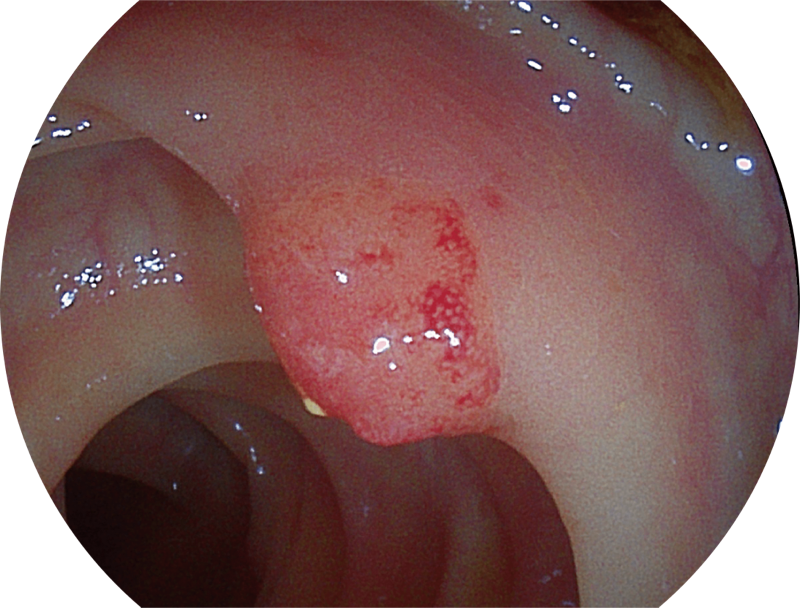

百万级像素高清传感器,1080P全高清视频信号输出,图像清晰。